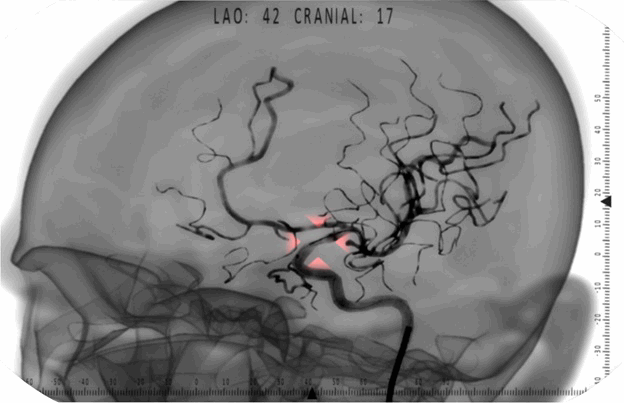

I work at the Eidos-Medicine ltd. company specializing in development of virtual medical training simulators. These are special software-hardware complexes capable of simulating the performance of various surgical interventions as part of an educational process for medical specialists. Using simulators allow medical students and interns to acquire their first practical profession skills before operating on live patients. Our project team develops an X-ray endovascular surgery simulator. This sphere embraces quite a number of various operations on blood vessels carried out under the control of fluoroscopy: angioplasty, stenting, spiral aneurysm embolization, and aortic aneurysm endoprosthesis replacement.

Our current team has been working on this project for one year and a half. The work is running its normal course. Consulting surgeons work with our analyst to coordinate on the surgical intervention tactics step by step and work out the requirements to the visualization system. The 3D artist uses CT-angiography, anatomical atlases, and surgeons' advice to develop new models for the database of medical cases emulated by the simulator. High-level programmers' duty is to implement fluoroscopy visualization, the physics of endovascular instruments movement inside arteries, and the logical analysis of a student's actions on the simulator to monitor the accuracy of accomplishing various intervention stages. Circuit engineers, microcontroller programmers, and design engineers ensure the correct work of various medical equipment emulators used in simulation; reading of data from the sensors and their primary processing and passing into the program. In response, the high-level part of the system prepares the information to be passed into the microcontroller, this information being used for implementing the hardware indication of the virtual intervention workflow and tactile feedback effects meant to make the training process as realistic as possible.

There were about 20 messages of this kind in the solution. Interestingly, this library has very high performance requirements. In earlier times, we used to count every multiplication operation and seek every opportunity to save resources in functions processing vectors and matrices. The loop in the code above runs through a great number of iterations - up to several dozens of thousands. It is included into the algorithms of the particles system which provides the angiography rendering. There are certain intricacies about visualizing the radiocontrast agent in the fluoroscopy image which have to do with the fact that blood vessels oriented at right angle to the frame plane look darker. X-rays in this case follow along the vessel, i.e. through a thick layer of absorbing medium, and therefore grow weaker and affect the film lesser in this projection. This effect is implemented in our program through a system of semi-transparent particles distributed inside the artery polygon mesh. Polygon meshes in our program are of a very high resolution; consequently, the amount of particles is also huge. It would be interesting to carry out an experiment to find out if we can win a millisecond or two by fixing these untidy code fragments. The compiler probably does this optimization automatically, but why not try forcing it?